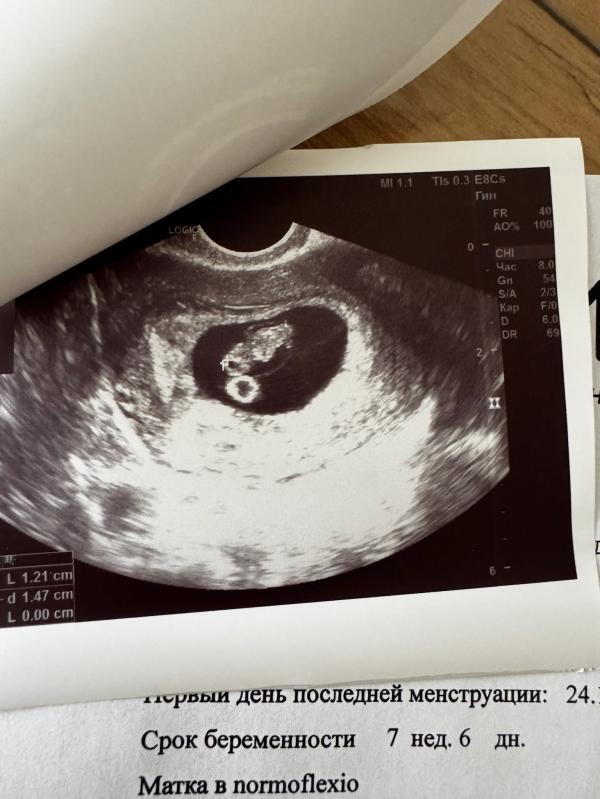

12.12.2024г Наша Малышка выбрала нас 🎀😍